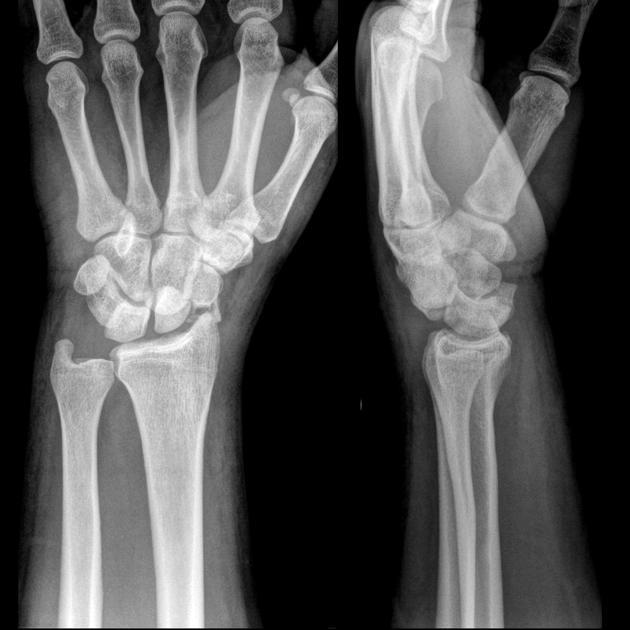

Diagnosis?

Trans-scaphoid perilunate dislocation.

This injury is associated with scapholunate and radiocapitate ligament tears.